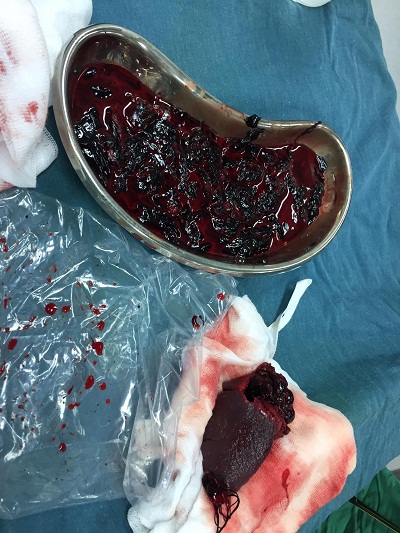

Máu vón cục sau khi được phẫu thuật

Trong quá trình phẫu thuật, quan sát thấy rất nhiều máu cục khắp bụng, nhiều máu loãng không đông. Thám sát thấy lách vỡ cực dưới gần hoàn toàn, đang chảy máu. Sau khi xin ý kiến BS Tạ Vũ Quỳnh- Trưởng khoa Ngoại tổng quát. Ê kip trực BS Trần Việt Hoàng – BS Võ Quang Huy quyết định cắt lách toàn phần.